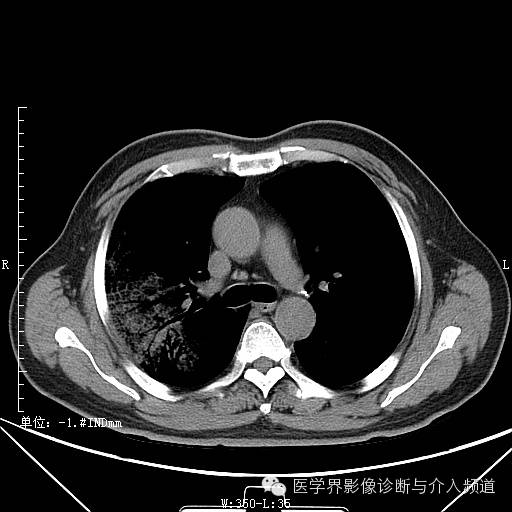

二次复查

二次复查:双肺多发实变、磨玻璃结构及粟粒结节,较前病变范围明显增大右侧并发气胸。